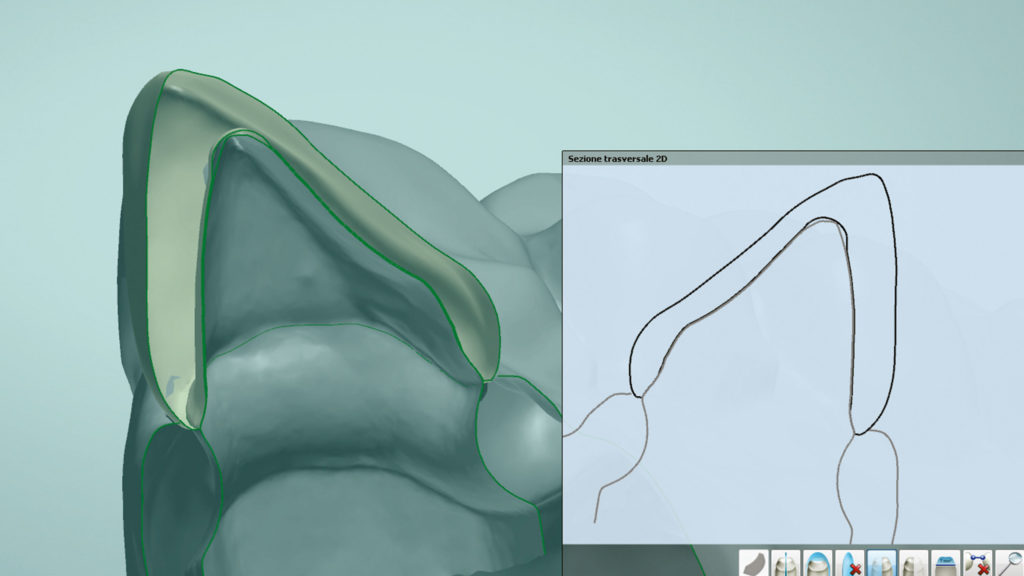

In der Software können wir uns im Schnittbild die verfügbare Dicke der zukünftigen Kronen anzeigen lassen, woraus sich wichtige Schlüsse über die mechanische Festigkeit der Versorgung ableiten lassen (Abb. 28). Die Farbanalyse hat zudem ergeben, dass keine komplizierten internen Charakteristika reproduziert werden müssen, und ein ästhetisches Ergebnis leicht zu erreichen ist.

Auf diesen Beobachtungen baut die Wahl unserer vollkeramischen Versorgungsform auf. Die Platz- und somit Festigkeitsverhältnisse, in Kombination mit der relativ unkomplizierten Ästhetik, bestätigen, dass eine komplett vollanatomische Versorgungsform realisiert werden kann. Zum Einsatz kommt dafür das kubische und daher „ultrahochtransluzente“ (glasartige) Katana Zirconia UTML, dessen positive lichtoptische Eigenschaften sich für einen Fall wie diesen ideal ausnutzen lassen.

Bei Vollkontur-Zirkonoxidversorgungen ist besonders hervorzuheben, dass sie das Zahnfleisch am wenigsten irritieren und sich somit sehr gut an die Gewebe adaptieren (vgl. Abb. 28).